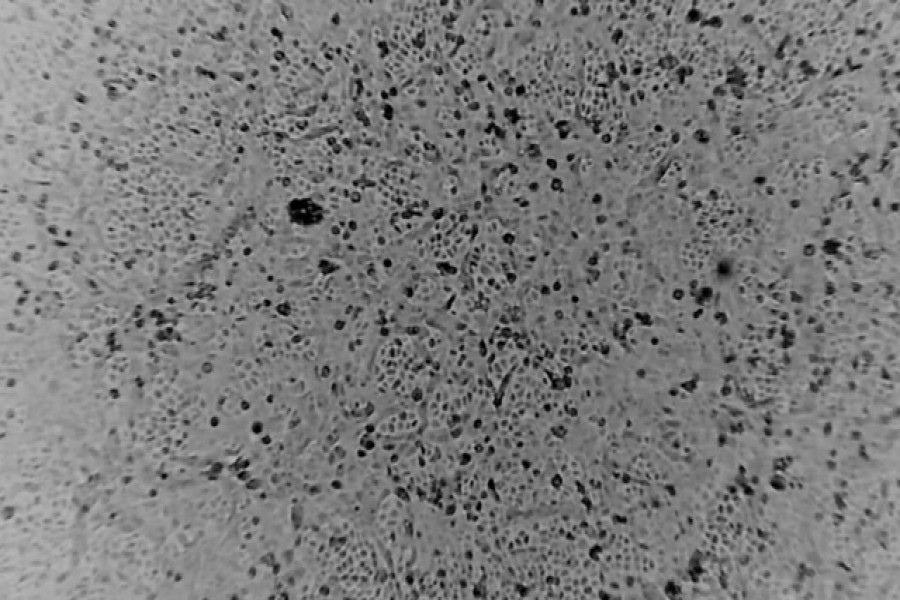

A team of scientists in Australia said on Wednesday they have successfully developed a lab-grown version of coronavirus, the first to be recreated outside of China, in a breakthrough that could help combat the global spread of the illness, reports Reuters.

The researchers at the Peter Doherty Institute for Infection and Immunity in Melbourne said they would share the sample, which was grown from an infected patient, with the World Health Organization and laboratories around the world.

The Australia-grown virus sample would be used to generate an antibody test, which would allow detection of the virus in patients who had not shown symptoms, as well as contributing to the creation of a vaccine, the institute said.

The virus was grown from a patient who had arrived at the institute on Jan 24, it added.